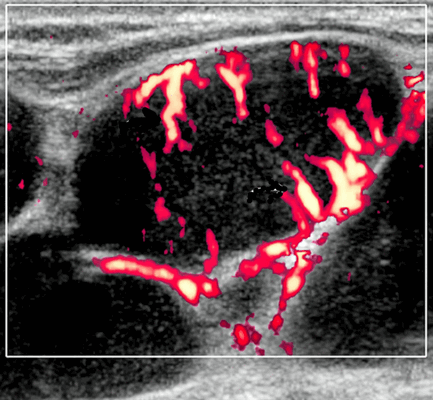

Энергетический допплер. Внутриочаговая васкуляризация. Хаотический / дезорганизованный или преимущественно периферический кровоток

Цветной допплер. Узловая НХЛ. Выраженная центральная или внутриузловая гиперваскуляризация. Паренхима при неходжкинской лимфоме более диффузная железистая гиперваскуляризация. Васкуляризация от умеренной до выраженной в плохо очерченных образованиях.

- Цветной допплер: смешанная васкуляризация с выраженным сосудистым рисунком и наличием периферической васкуляризации. Периферическая сосудистая сеть редко встречается в узлах НХЛ

Цветовой допплер: смешанная сосудистая сеть с выраженными внутриузловыми сосудами и наличием периферической сосудистой системы. Одна только периферическая сосудистая сеть редко встречается в узлах НХЛ. Спектральный допплер: переменное интранодальное внутрисосудистое сопротивление, которое носит неспецифический характер.